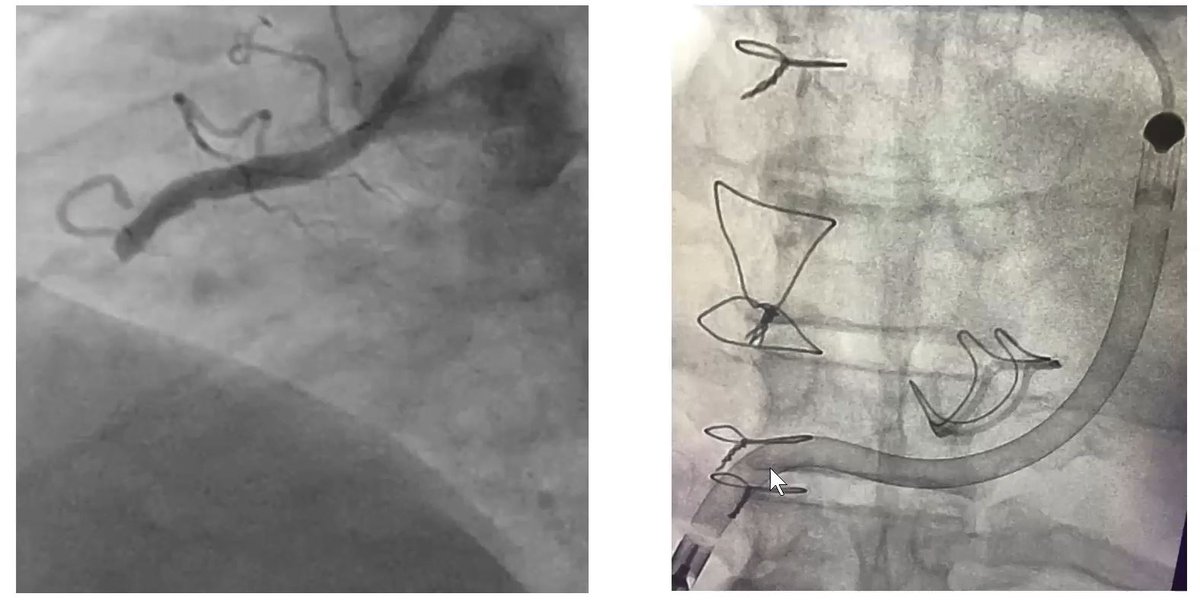

66. This patient continued to be in shock. Here we see the occluded RCA of the STEMI. RV infarct shock needed RV support. In this case, Impella RP. You can see it go up the RA, through the RV & into the PA. The device provided very good RV support.